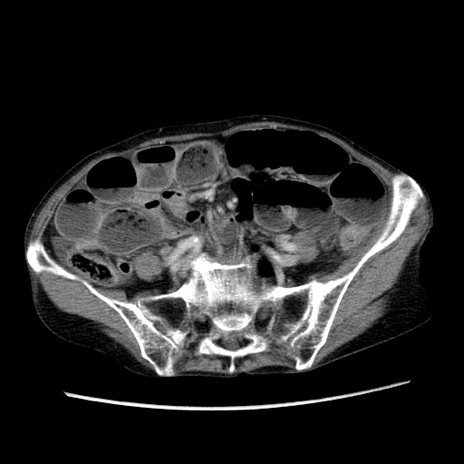

症例25(横断像)

【症例】80歳代女性

【主訴】胸のつかえ感

【現病歴】約9時間前に食後から胸のつかえた感じあり、嘔吐あり、来院。

【既往歴】胃癌(全摘)、胆摘、虫垂炎

【身体所見】心窩部に圧痛あり、反跳痛なし。

【データ】WBC 5700、CRP 0.05